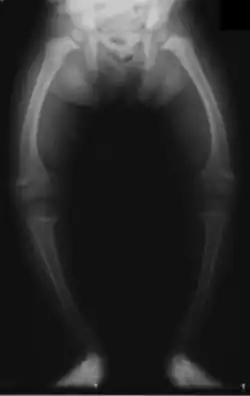

Rickets, a childhood disease, is characterized by impeded growth and soft, weak, deformed long bones that bend and bow under their weight as children start to walk. Maternal vitamin D deficiency can cause fetal bone defects from before birth and impairment of bone quality after birth.[81][82] Rickets typically appear between 3 and 18 months of age.[83] This condition can be caused by vitamin D, calcium or phosphorus deficiency.[84] Vitamin D deficiency remains the main cause of rickets among young infants in most countries because breast milk is low in vitamin D, and darker skin, social customs, and climatic conditions can contribute to inadequate sun exposure. A post-weaning Western omnivore diet characterized by high intakes of meat, fish, eggs and vitamin D fortified milk is protective, whereas low intakes of those foods and high cereal/grain intake contribute to risk.[85][86][87] For young children with rickets, supplementation with vitamin D plus calcium was superior to the vitamin alone for bone healing.[88][89]

.jpg)